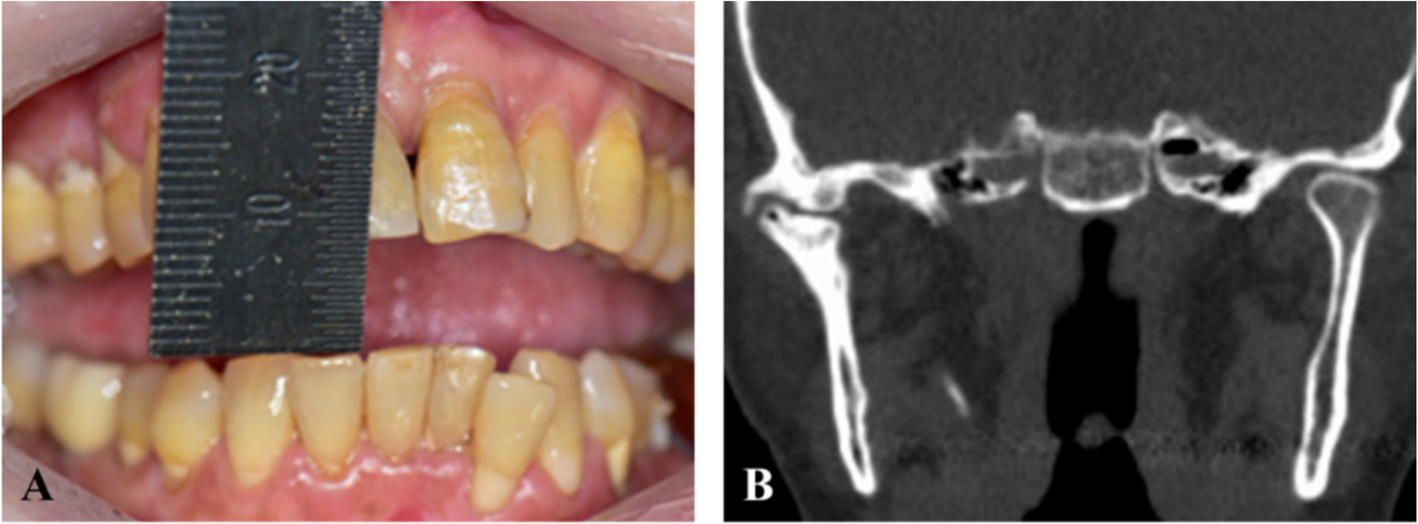

Radiological features of Stafne mandibular bone cavity in panoramic image and cone beam computed tomography

Stafne mandibular bone cavity (SMBC) is an asymptomatic radiolucent lesion observed in the mandible on X-ray images, with ...